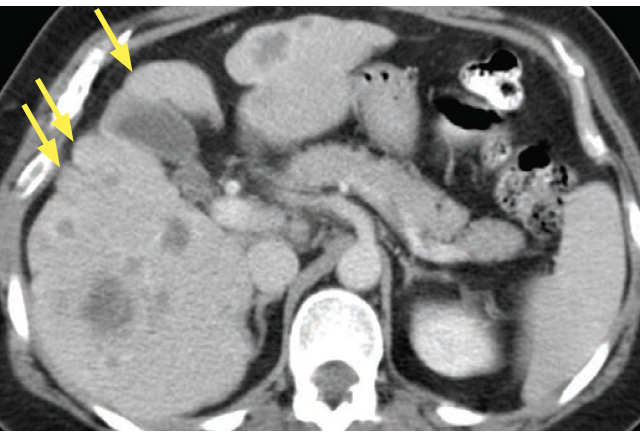

Dx?

Pseudocirrhosis

Macronodular liver contour from multiple scirrhous hepatic metastases (mimic cirrhosis)

MCC is treated breast cancer

Capsular retraction is charactersitic when present